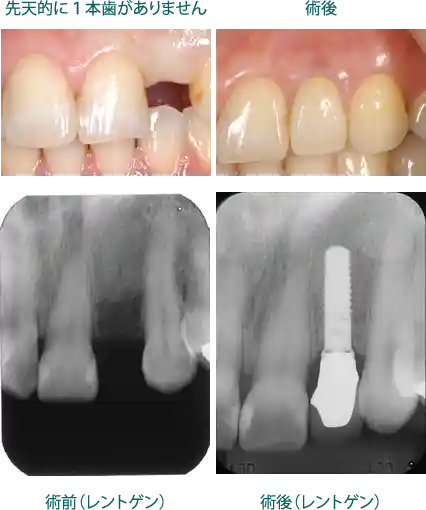

ケーススタディ3:先天的に1本歯がない患者様

インプラントを埋入した症例

このケースは先天的に歯が欠損していました。レントゲンでもわかるように骨の量も十分です。この様な場合、骨の造成の必要がありません。治療期間も短く、費用も少なくて済みます。

① 費用:¥479,600【税込】~

②リスク:骨量があっても、必ずインプラントと骨が統合するとは限りません。チタンアレルギーのある方には使用できません。